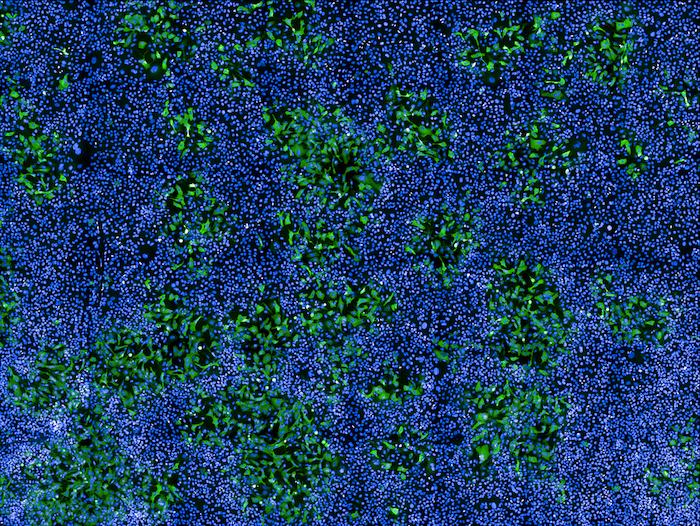

Human cells infected with MPXV

Human cells infected with MPXV (in green) among non-infected cells (nuclei in blue). Confocal microscopy image. © Institut Pasteur / Mathieu Hubert and Olivier Schwartz

Credit: © Institut Pasteur / Mathieu Hubert and Olivier Schwartz